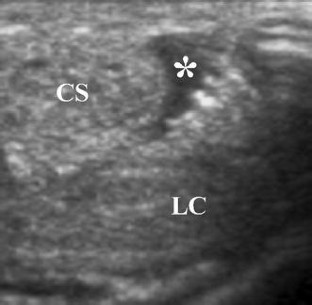

Fig. 2